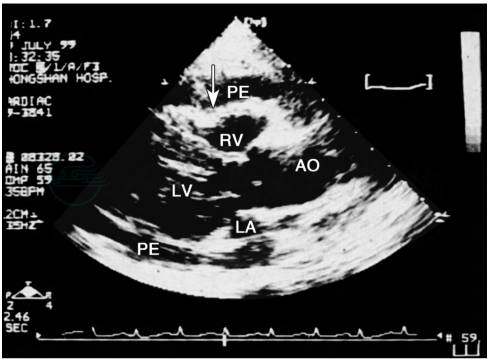

图2 心包积液伴心脏压塞的二维超声心动图表现

胸骨旁长轴切面,箭头示右室前壁舒张期塌陷。PE.心包积液;RV.右心室;LV.左心室;LA.左心房;AO.主动脉。